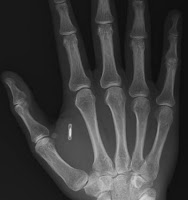

So, it has been 6 months since i had my implant put in. Aside from occasional irritation, usually due to nonstop typing all day, I am doing just fine. No cancer, rejection, or government tracking. Since i am a diabetic, i still have a small dot on my hand from the hole that was made, but it is almost invisible at this point. I've been using it to start my car for about as long and I have to say that it works flawlessly.